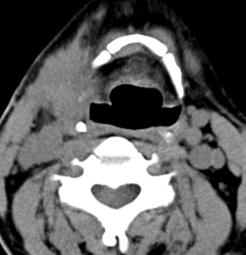

标题: CT17168:会诊,颈部包块 [打印本页]

标题: CT17168:会诊,颈部包块

怎么不传病史呢?右侧颌下腺炎症?

考虑:右侧颌下腺炎症。建议强化。

不排除右侧颌下腺恶性肿瘤可能;建议行进一步检查。

考虑:右侧颌下腺炎症可能。

我也是报的颌下腺炎症。